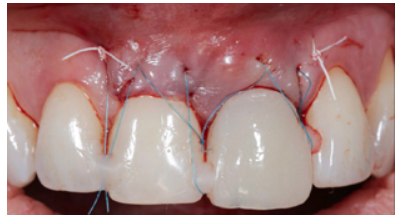

Clinical case: A 32-year-old female patient who attended for a possible root fracture of the upper left central incisor (ULCI), accompanied by a periodontal abscess at the bottom of the vestibule of the same tooth. A clinical and radiological examination established that the prognosis of the ULCI was unfavourable for conservative treatment. After evaluating the clinical features of the case, the treatment plan to extract the ULCI followed immediately by an osseointegrated implant (OII) and loading of a provisional prosthesis on the implant.

Conclusions: Rehabilitation on implants in situations of tooth loss in the aesthetic anterior sector, especially in young patients, requires a multidisciplinary treatment plan to extract the tooth and insert an OII in the correct 3-dimensional position. Various aspects need to be taken into account for this, particularly the residual remaining bone, the position of the gingival margin and preservation and conditioning of the peri-implant hard and soft tissues by means of grafts and proper handling of provisional prosthesis, until an ideal emergence profile and gingival contour is achieved before the final crown.

The benefits of immediate loading include a marked reduction in surgical interventions, less temporary dilation of the treatment and even better psychological and social wellbeing for the patient. In cases with a significant aesthetic requirement, immediate loading or provisionalisation, and post-extraction placement of the OII minimise alterations due to tooth loss and maintain the emergence profile, soft tissue contour and gingival papillae5-7.

Different protocols have also been established for the management of the anterosuperior aesthetic sector, in addition to performing the immediate implant and provisional crown, including placing material between the OII and the buccal cortical to minimise possible collapse and the management of peri-implant soft tissue8-11.